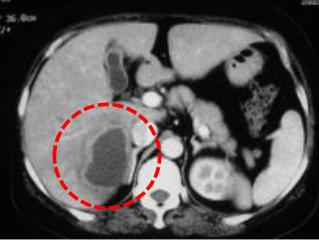

寒颤高热8天,CT检查发现肝内巨大脓肿

治疗前

经介入引流后脓肿消失,体温恢复正常。

治疗后